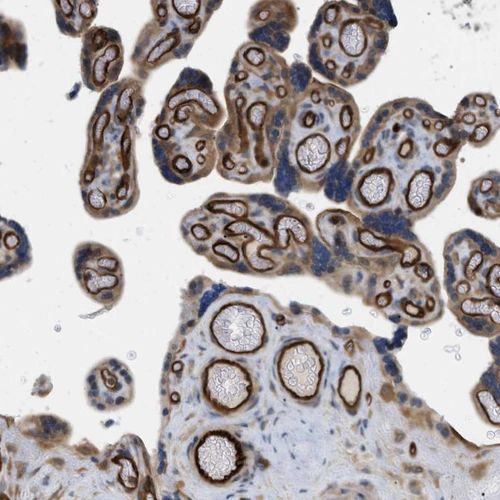

Immunohistochemical staining of human placenta shows strong cytoplasmic positivity in decidual cells.